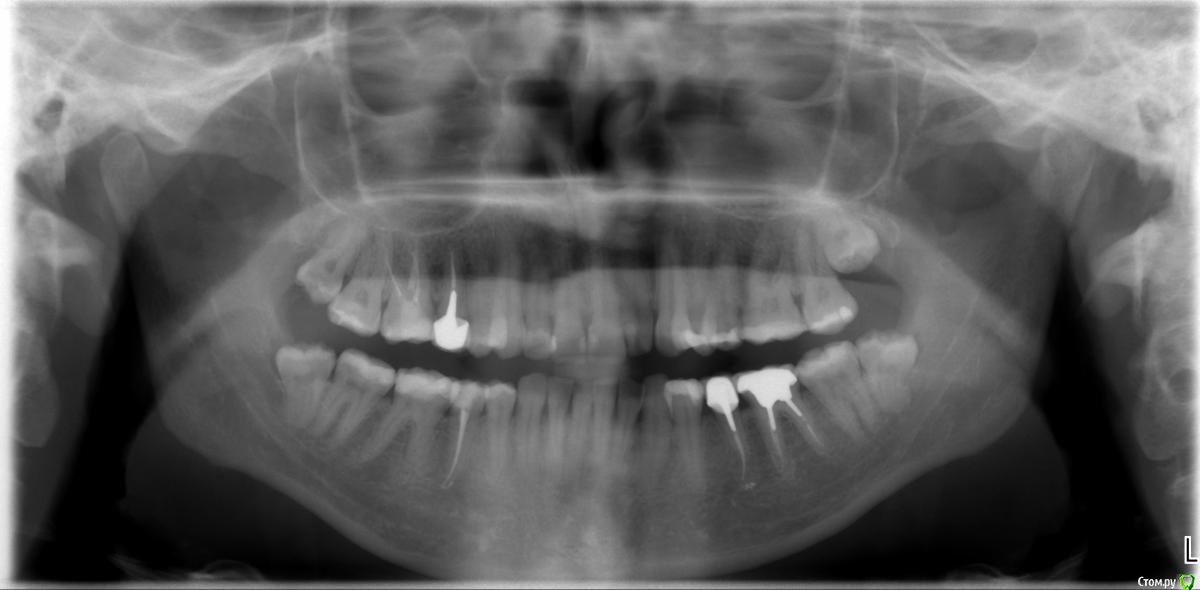

Metanira Опубликовано 17 апреля, 2015 Поделиться Опубликовано 17 апреля, 2015 Добрый день, дорогие стоматологи!Прилагаю снимок, сделанный в апреле этого года и фотографии. После него вылечена 4.4, так как вывалилась пломба. Очень хочу узнать ваше мнение по следующим вопросам и буду очень благодарна за любые ответы, не обязательно на все вопросы)Какие зубы стоит начать лечить в первую очередь? У меня очень много пломб, но менять их все не хочется, так как скоро от зубов ничего не останется( Пока планирую вылечить 2.1. В клинике к лечению посоветовали зубы: 14, 16, 17, 25, 26, 27, 34 (оверлей), 46 (оверлей), 47 (оверлей). С чего начать? Стоит ли пломбировать пришеечный кариес на нижних зубах? Врач рекомедовал лечить все зубы с 33 по 43. Они никак не беспокоят, боюсь лечить, так как боюсь, что появится чувствительность. Стоит ли пользоваться в моем случае монопучковой щеткой? Она у меня есть, но мне кажется, она все-таки жестковата. Что-то странное у меня с пломбой на 44-45 зубах сверху, она одна на 2 зуба, это как-то оправдано?) Какая щетка Cura Prox по вашему мнению лучше 5460 (один стоматолог сказал, что лучше ее использовать, так как чем мягче, тем лучше) или же 3960 (другой стоматолог посоветовал мне именно ее из-за сильного налета, после нее зубы кажутся белее, но боюсь, что для эмали она менее безопасна, чем 5460). Я курю и пью чай, зубы чищу регулярно, но вот такой вот налет. У меня щелкает правый сустав челюсти, стоит ли использовать Аква Сплинт или что-нибудь подобное ночью?Брекеты носить не планирую, так как мои зубы и эмаль этого точно не переживут.Заранее всех благодарю! Ссылка на комментарий

krokomot Опубликовано 17 апреля, 2015 Поделиться Опубликовано 17 апреля, 2015 Спасибо за ответ. Ошиблась, 2.2 как раз и хочу сделать в первую очередь. Эстетически меня вообще не беспокоит пришеечный кариес, поэтому если не стоит его трогать, то и не буду. Просто, как вы поняли, мне чуть ли не каждый зуб пломбировать или перепломбировывать, поэтому и хочу узнать, действительно ли все это необходимо или что-то можно не трогать. Ну и вопросы вроде довольно конкретные.... 1 решить сложно, что первее, не видя ситуации во рту, по ОПТГ ничего критичного не видно, там где в зубах пломбированы каналы стоит зделать прицельные снимки на придмет отсутствия околокорневой патологии. Так что думаю очередность на ваш выбор2. надо смотреть по ситуации если поврхностное поражение можно обойтись сошлифовыванием и полировкой затем минерализующая терапия и чувствительность, если она появиться - пройдет. А если процесс не поверхностный нужно реставрировать. Смысла в монопучковой щетке не вижу. Должна быть щетка средней жесткости, паста со фтором, правильная техника чистки зубов, зубная нить и ирригатор тогда с гигиеной проблем не будет, но надо делать профессиональную гигиену 2 раза в год.3. Пломб на 2 зуба быть не должно. И ответьте почему вы решили, что она на 2 зуба?4.Ответил в пункт 25. Шина возможно несколько улучшит ваше состояние, но проблемы с прикусом не решит, так что потихоньку готовтесь к иправлению прикуса. Ссылка на комментарий